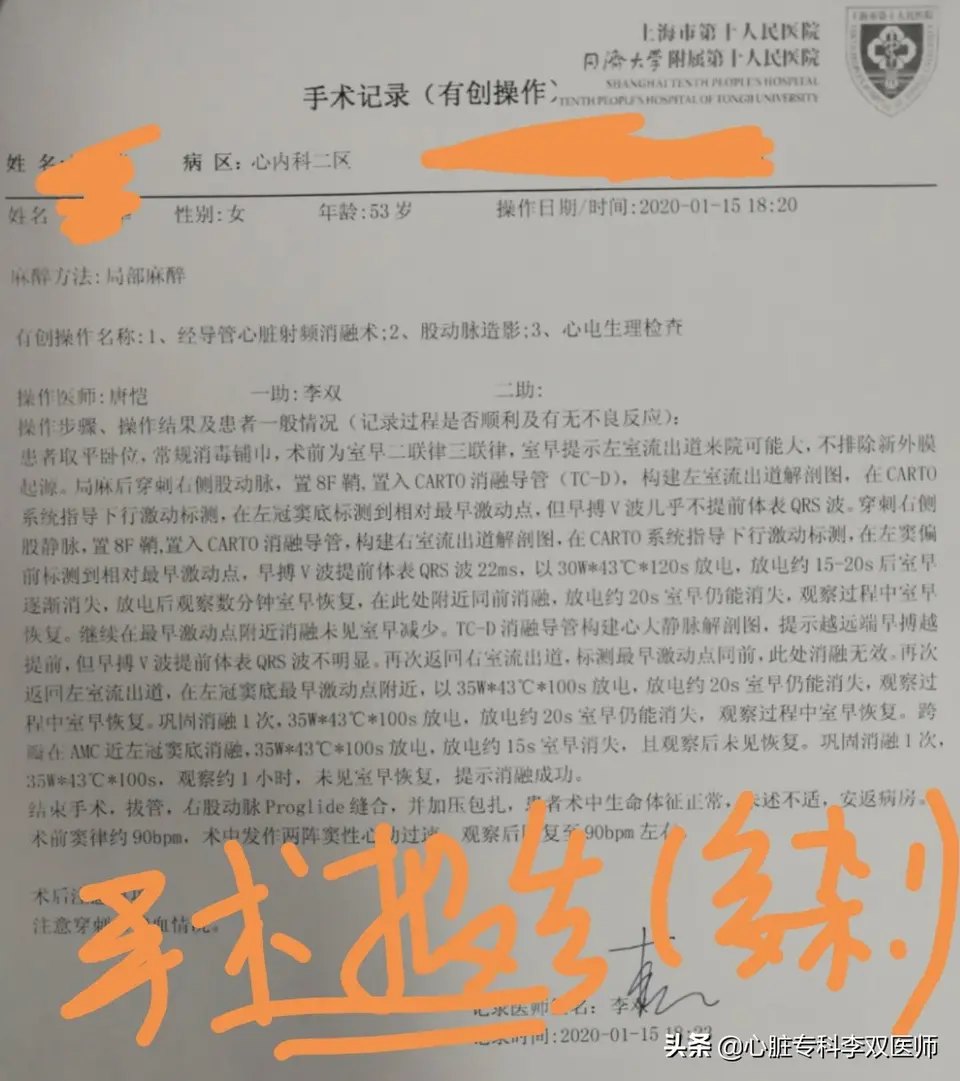

前天给一个外地来就诊的病人做了难度很高的“心外膜室早”消融的病例,病人一年前在杭州某三甲医院曾行消融失败,这一年来因为笼罩在“频发室早”的阴影下,患者有了明显的心理问题。这次我们标测的情况和上次外院消融情况完全一致,只是坚持又带有一点运气的在非传统的消融位置(解剖位置,而不是最早激动位置)尝试了消融,结果异常的顺利,术中忐忐忑忑观察了一小时无复发。今天患者顺利出院,术后24小时心电图提示的室早仅2次(一天的心跳是约10万次,1000次以内的早博没有意义),比机器的误差都小,而术前是1.4—2.8万次,是万!万!万!。坚持就是胜利,坚持带来好运!